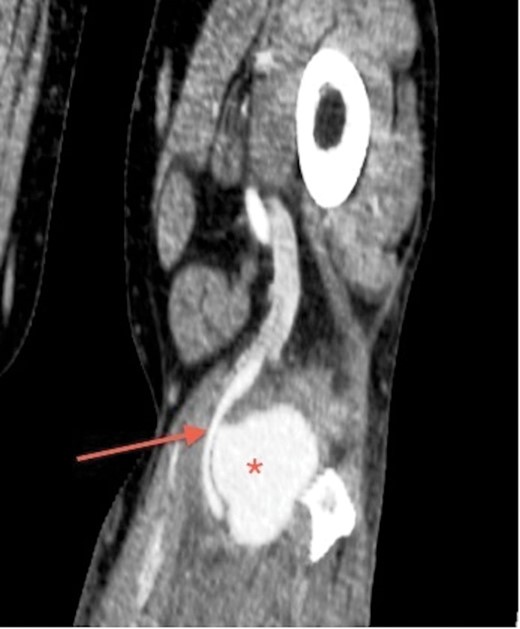

His laboratory reports for full blood count, urea and electrolytes were normal. In view of the ultrasound findings, a CT angiogram of lower limbs was performed. It confirmed 6 × 5 × 4 cm pseudoaneurysm, compressing and displacing his left popliteal artery. However, three-vessel run-off below the knee was satisfactory (Figs 1 and2).

CT angiogram of the left leg, coronal section, shows popliteal pseudoaneurysm (asterisk), communicating and displacing the popliteal artery (arrow).